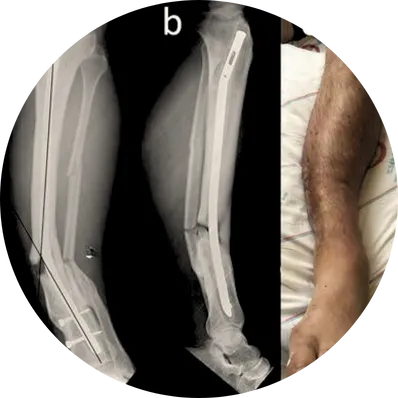

The procedure is performed under regional or general anesthesia. The surgeon reopens the previous incision to access the implant and carefully removes plates, screws, rods, or nails without disturbing the healed bone. Specialized tools are used to gently disengage the hardware while protecting surrounding muscles and nerves.

If infection or tissue irritation is present, the surgeon cleans the area, removes infected tissue, and washes the surgical site thoroughly to promote healing and prevent recurrence.

In cases where bone strength is inadequate or removal may compromise stability, temporary support such as splints, braces, or casts may be provided until full recovery.